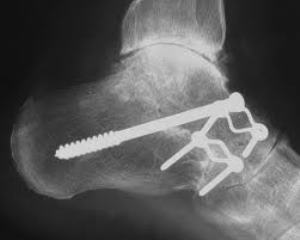

При проведении операции первым этапом становится вскрытие поврежденного сочленения. Затем в один из его полюсов вставляют ограничитель. Его готовят заранее из кости, полимерных материалов или мягких тканей. Этот ограничитель предназначен для ограничения подвижности.

Как правило, чтобы надежнее стабилизировать сустав артрориз проводят вместе с артодезом соседних суставов. Стабилизаторы иногда используют и для артродеза. При этом потребуется более длинный отрезок кости. Его вбивают в соседнее сочленение.

Однако, есть ряд возможных осложнений. Если трансплантант будет центрирован неправильно, тон может занять неправильное положение и привести к некорректной работе сустава. Кроме того, бывают случаи перелома кости, который становится серьезной патологией, так как срастается она быстро и неправильно.